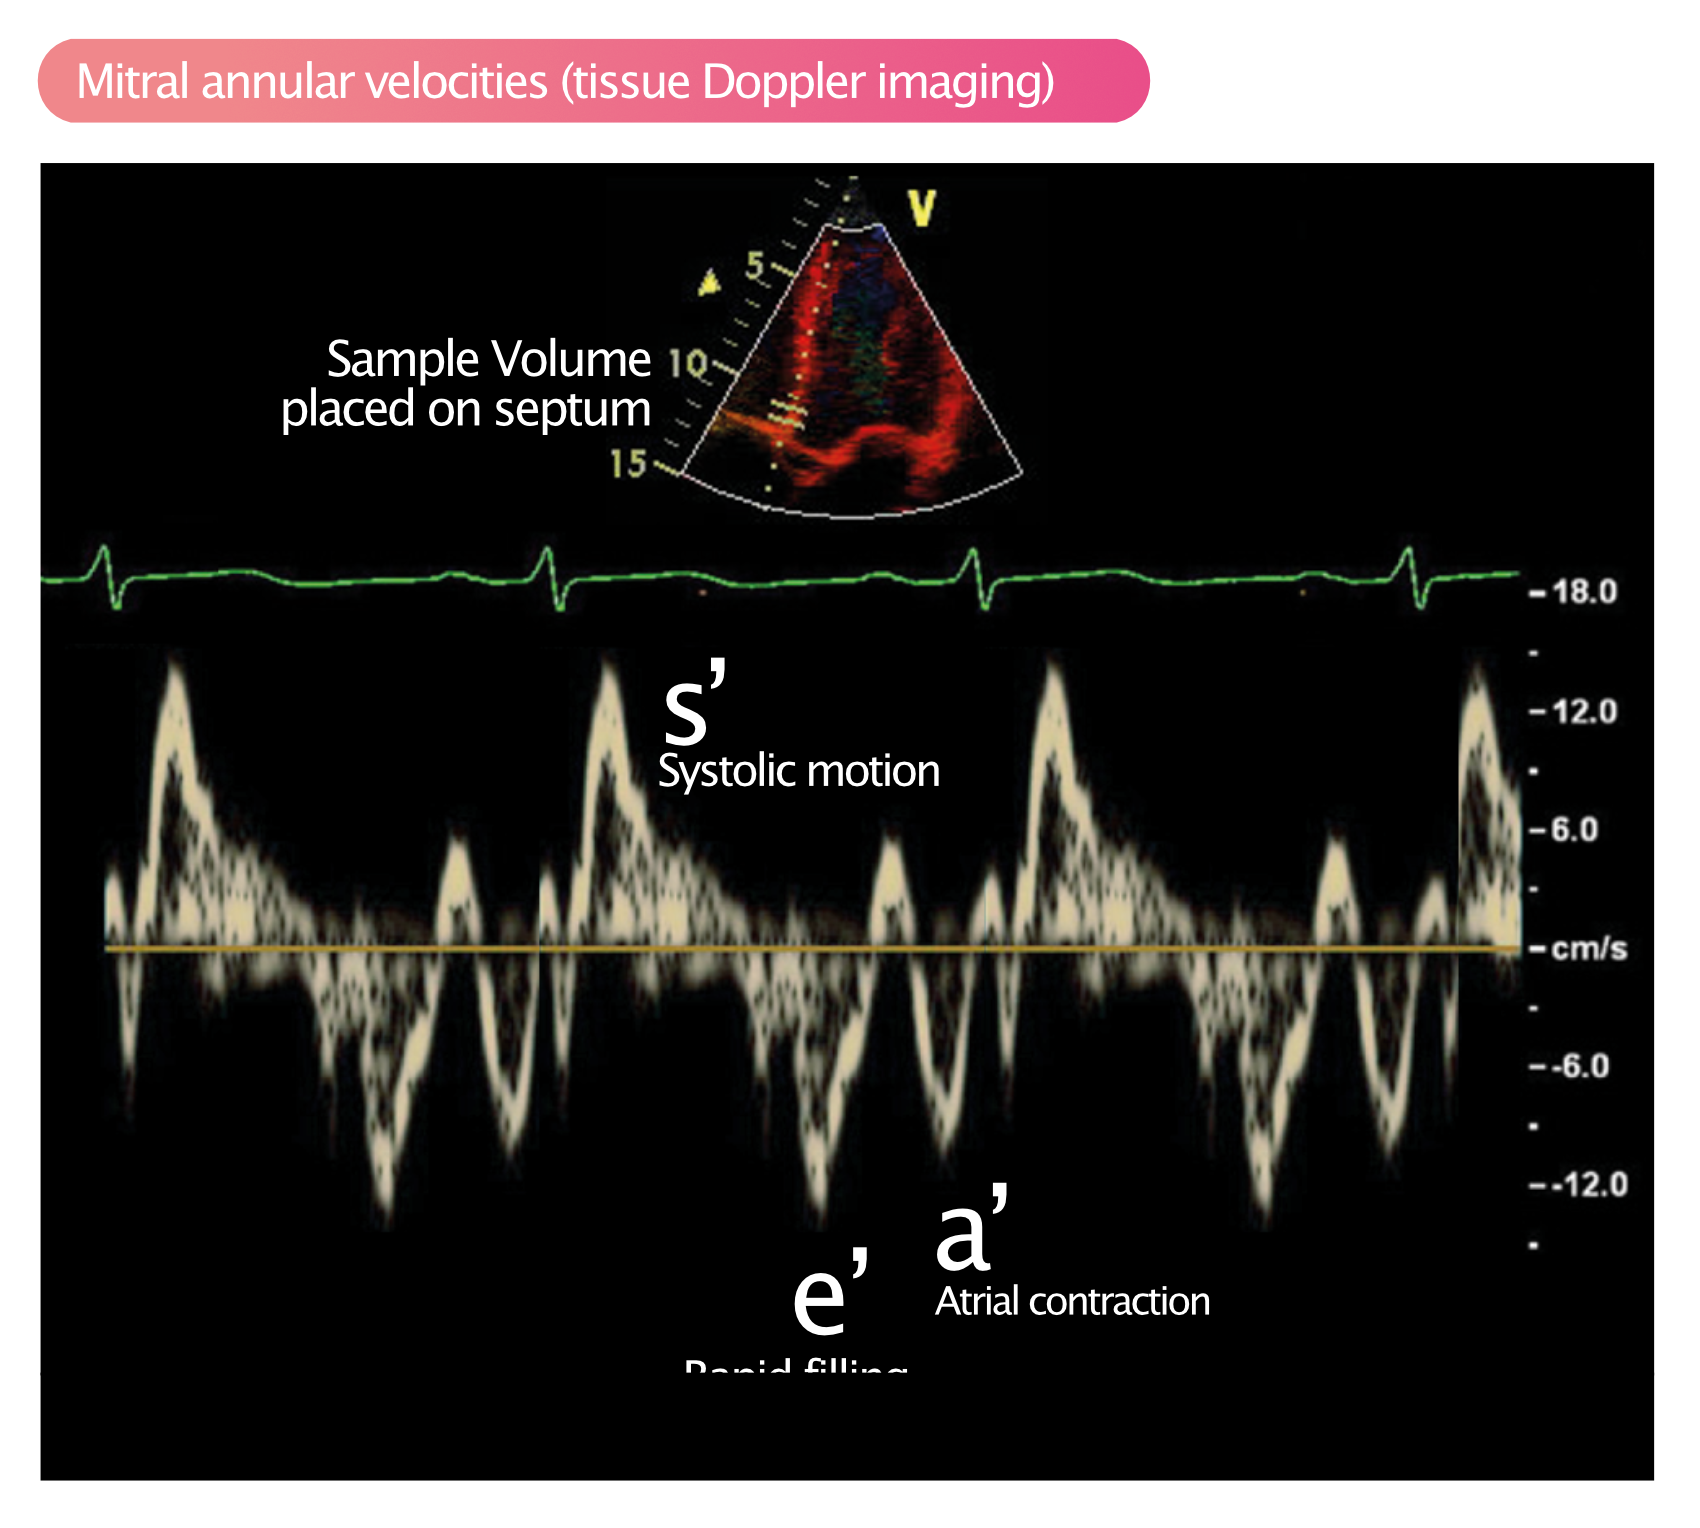

mitral-annular-velocity-tissue-doppler-diastolic-function-dysfunction-echocardiography